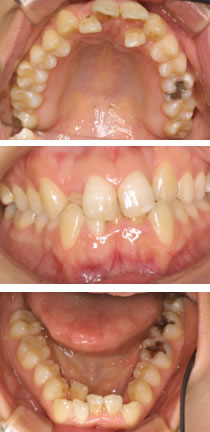

【症例2 歯列】

症例2 歯列 治療前 症例2 歯列 治療後

Before After